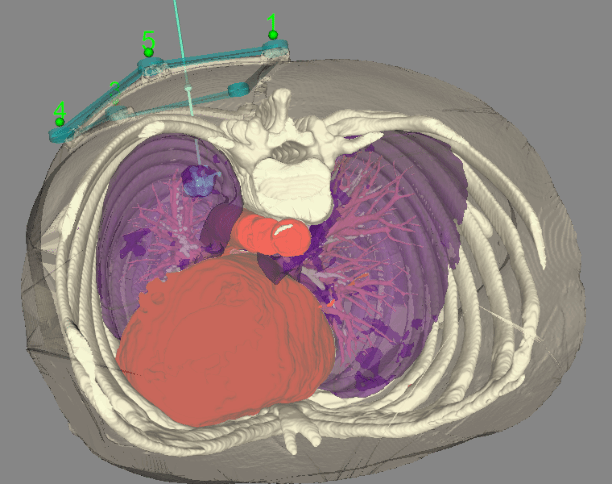

本次完成的两例手术均体现出机器人辅助穿刺的系统优势:患者一为乳腺癌新辅助治疗中,左肺下叶存在10mm微小结节;患者二为右肺下叶后基底段15mm结节。术前通过CT扫描于体表放置定位标记,系统自动识别并重建肺部三维模型,医生据此规划穿刺路径。术中,机器人机械臂在光学导航引导下精准定位,辅助术者将同轴穿刺针一次到位。CT复查确认针尖抵达目标病灶,活检取材满意。两例手术均仅耗时约十分钟,术后仅见少量肺内出血,未发生气胸等并发症,患者无明显不适。

目前,CT引导下的肺肿瘤消融、结节定位及穿刺活检等技术的核心均在于穿刺精度。传统方式高度依赖术者经验,常需多次扫描调针,时间长、辐射多,并发症风险较高。而机器人穿刺导航系统可精准复现规划路径,通过机械臂稳定操作,显著提升首次穿刺成功率,减少血管损伤,缩短手术时间,降低并发症发生率,为提高诊断符合率提供了可靠保障。该系统尤其适用于微小结节、解剖位置特殊(如肋骨遮挡、邻近重要血管及气道)以及下肺病灶的穿刺与消融治疗,有力支持了高难度病灶的精准诊疗。